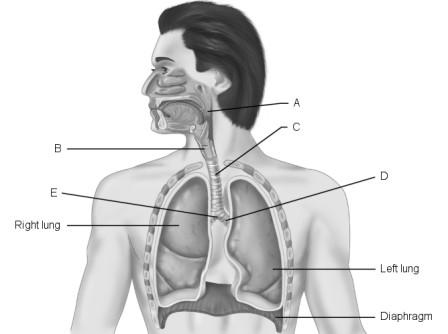

The parietal pleura lines the thoracic wall.

Main (primary) bronchus.

Larynx.

B